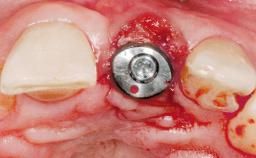

Immediate Flapless Placement of an Implant in a Maxillary Left Central Incisor Site

A 42-year-old female patient was referred to our clinic at the School of Dentistry of the University of São Paulo in November 2004, presenting a deficient restoration in the upper left central incisor. The clinical examination revealed no gingival retraction or any signs of gingival inflammation and, therefore, previous periodontal treatment was not considered. The patient presented a high lip line at full smile and a thin tissue biotype. This combination characterized a high-risk situation from an anatomic point of view, which required careful preoperative planning and cautious surgical execution.

Type of Implants One-Piece

Attachment One-Piece

Placement Protocol Immediate implant placement

Tooth Site Maxillary incisor or canine

Socket Morphology Single-root socket

Socket Integrity Sufficient, with intact bone walls